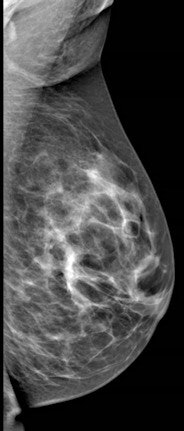

Breast cancer findings include masses, calcifications, developing asymmetry, and skin thickening, which is often imperceptible, Shaheen said. For whatever reason the patient is called back -- a finding on mammography, a clinical finding, or a patient discovering a symptom -- the diagnostic path generally begins with multimodality imaging, followed by image-guided biopsy. Then comes the critical rad-path correlation and, ultimately, assessment of cancer pathology and hormonal status before deciding on treatment, which greatly depends on the individual case.

According to the 2013 American College of Radiology (ACR) guidelines, breast MRI should be performed for screening high-risk patients, as well as those with a new breast malignancy, following a 2007 report in the New England Journal of Medicine on MRI's ability to find cancer in the contralateral breast. It should also be used to screen patients with breast augmentation, which presents difficulties such as mammographically occult regions, or cancer tracking the contour of the implant, Shaheen said.

For confirmed cancers, MRI can be used to assess the extent of disease such as ductal carcinoma in situ, for additional evaluation of imaging or clinical findings, and for problem-solving.